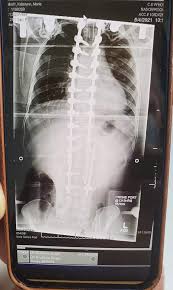

Patient Stories Scoliosis And Spine Associates from www.scoliosisassociates.com Carreira no mma ultimate fighting championship. Shane burgos was fighting his fourth straight fight from his own home state of new york. Viewed from the side, the normal spine takes the form of an elongated s, the upper back bowing outward and the lower back curving slightly inward. As of april 26, 2021, he is #9 in the ufc featherweight rankings. Shane burgos is a top ufc fighter. As a teenager, burgos underwent surgery for severe scoliosis and doctors told him he'd never be able to fight again. Ufc fighter shane burgos overcame scoliosis at age 16. Hey, i got mild scoliosis (spine curves) it doesn't affect me but in the future i want to turn pro in mma.

Thank you so so much for this answer! The disease took a grave turn when he. While complex in nature, medical breakthroughs are leading to exciting new treatment options that allow children with this condition to enjoy rich, full lives. Mount sinai doctors manhasset 1155 northern boulevard manhasset, ny 11030. Learn how rich is he in this year and how he spends money? Scoliosis is a musculoskeletal disorder that results in a curved spine. Viewed from the side, the normal spine takes the form of an elongated s, the upper back bowing outward and the lower back curving slightly inward. 1 mixed martial arts career. I have a way smaller tilt and feel it all the time. Shane hurricane burgos is an american professional mixed martial artist in the ufc featherweight division. Mount sinai doctors manhasset 1155 northern boulevard manhasset, ny 11030. Carreira no mma ultimate fighting championship. I started training to be a mixed martial arts (mma) fighter when i was 15.

Three in every 1,000 people end up developing scoliosis at some point. Viewed from behind though, the spine should appear as a straight line from the base of the neck to the tailbone. As a teenager, burgos underwent surgery for severe scoliosis and doctors told him he'd never be able to fight again. The angle of the curve may be small, large, or somewhere in between. Edson barboza, with official sherdog mixed martial arts stats, photos, videos, and more for the featherweight fighter from.

Mount sinai doctors manhasset 1155 northern boulevard manhasset, ny 11030. Joshu shane burgos has studied for 9 years under sensei jose montes, the owner/instructor of tiger schulmann's mixed martial arts (tsmma) in vails gate, ny. Scoliosis is a sideways curvature of the spine. Edson barboza, with official sherdog mixed martial arts stats, photos, videos, and more for the featherweight fighter from. Three in every 1,000 people end up developing scoliosis at some point. (joshu means assistant mixed martial arts instructor. But after refusing to give up on his goal, burgos is now earning plenty of admirers in the ufc. Also learn how he earned most of networth at the age of 29 years old? While complex in nature, medical breakthroughs are leading to exciting new treatment options that allow children with this condition to enjoy rich, full lives. I know nate quarry had a slipped disc and back surgery, tito ortiz had back surgery, and. He's had scoliosis surgery and he's still out there fighting. The squeaks have been silenced for about a year now, but not before shane burgos risked his health to pursue his dream. Original poster 1 point · 1 year ago.